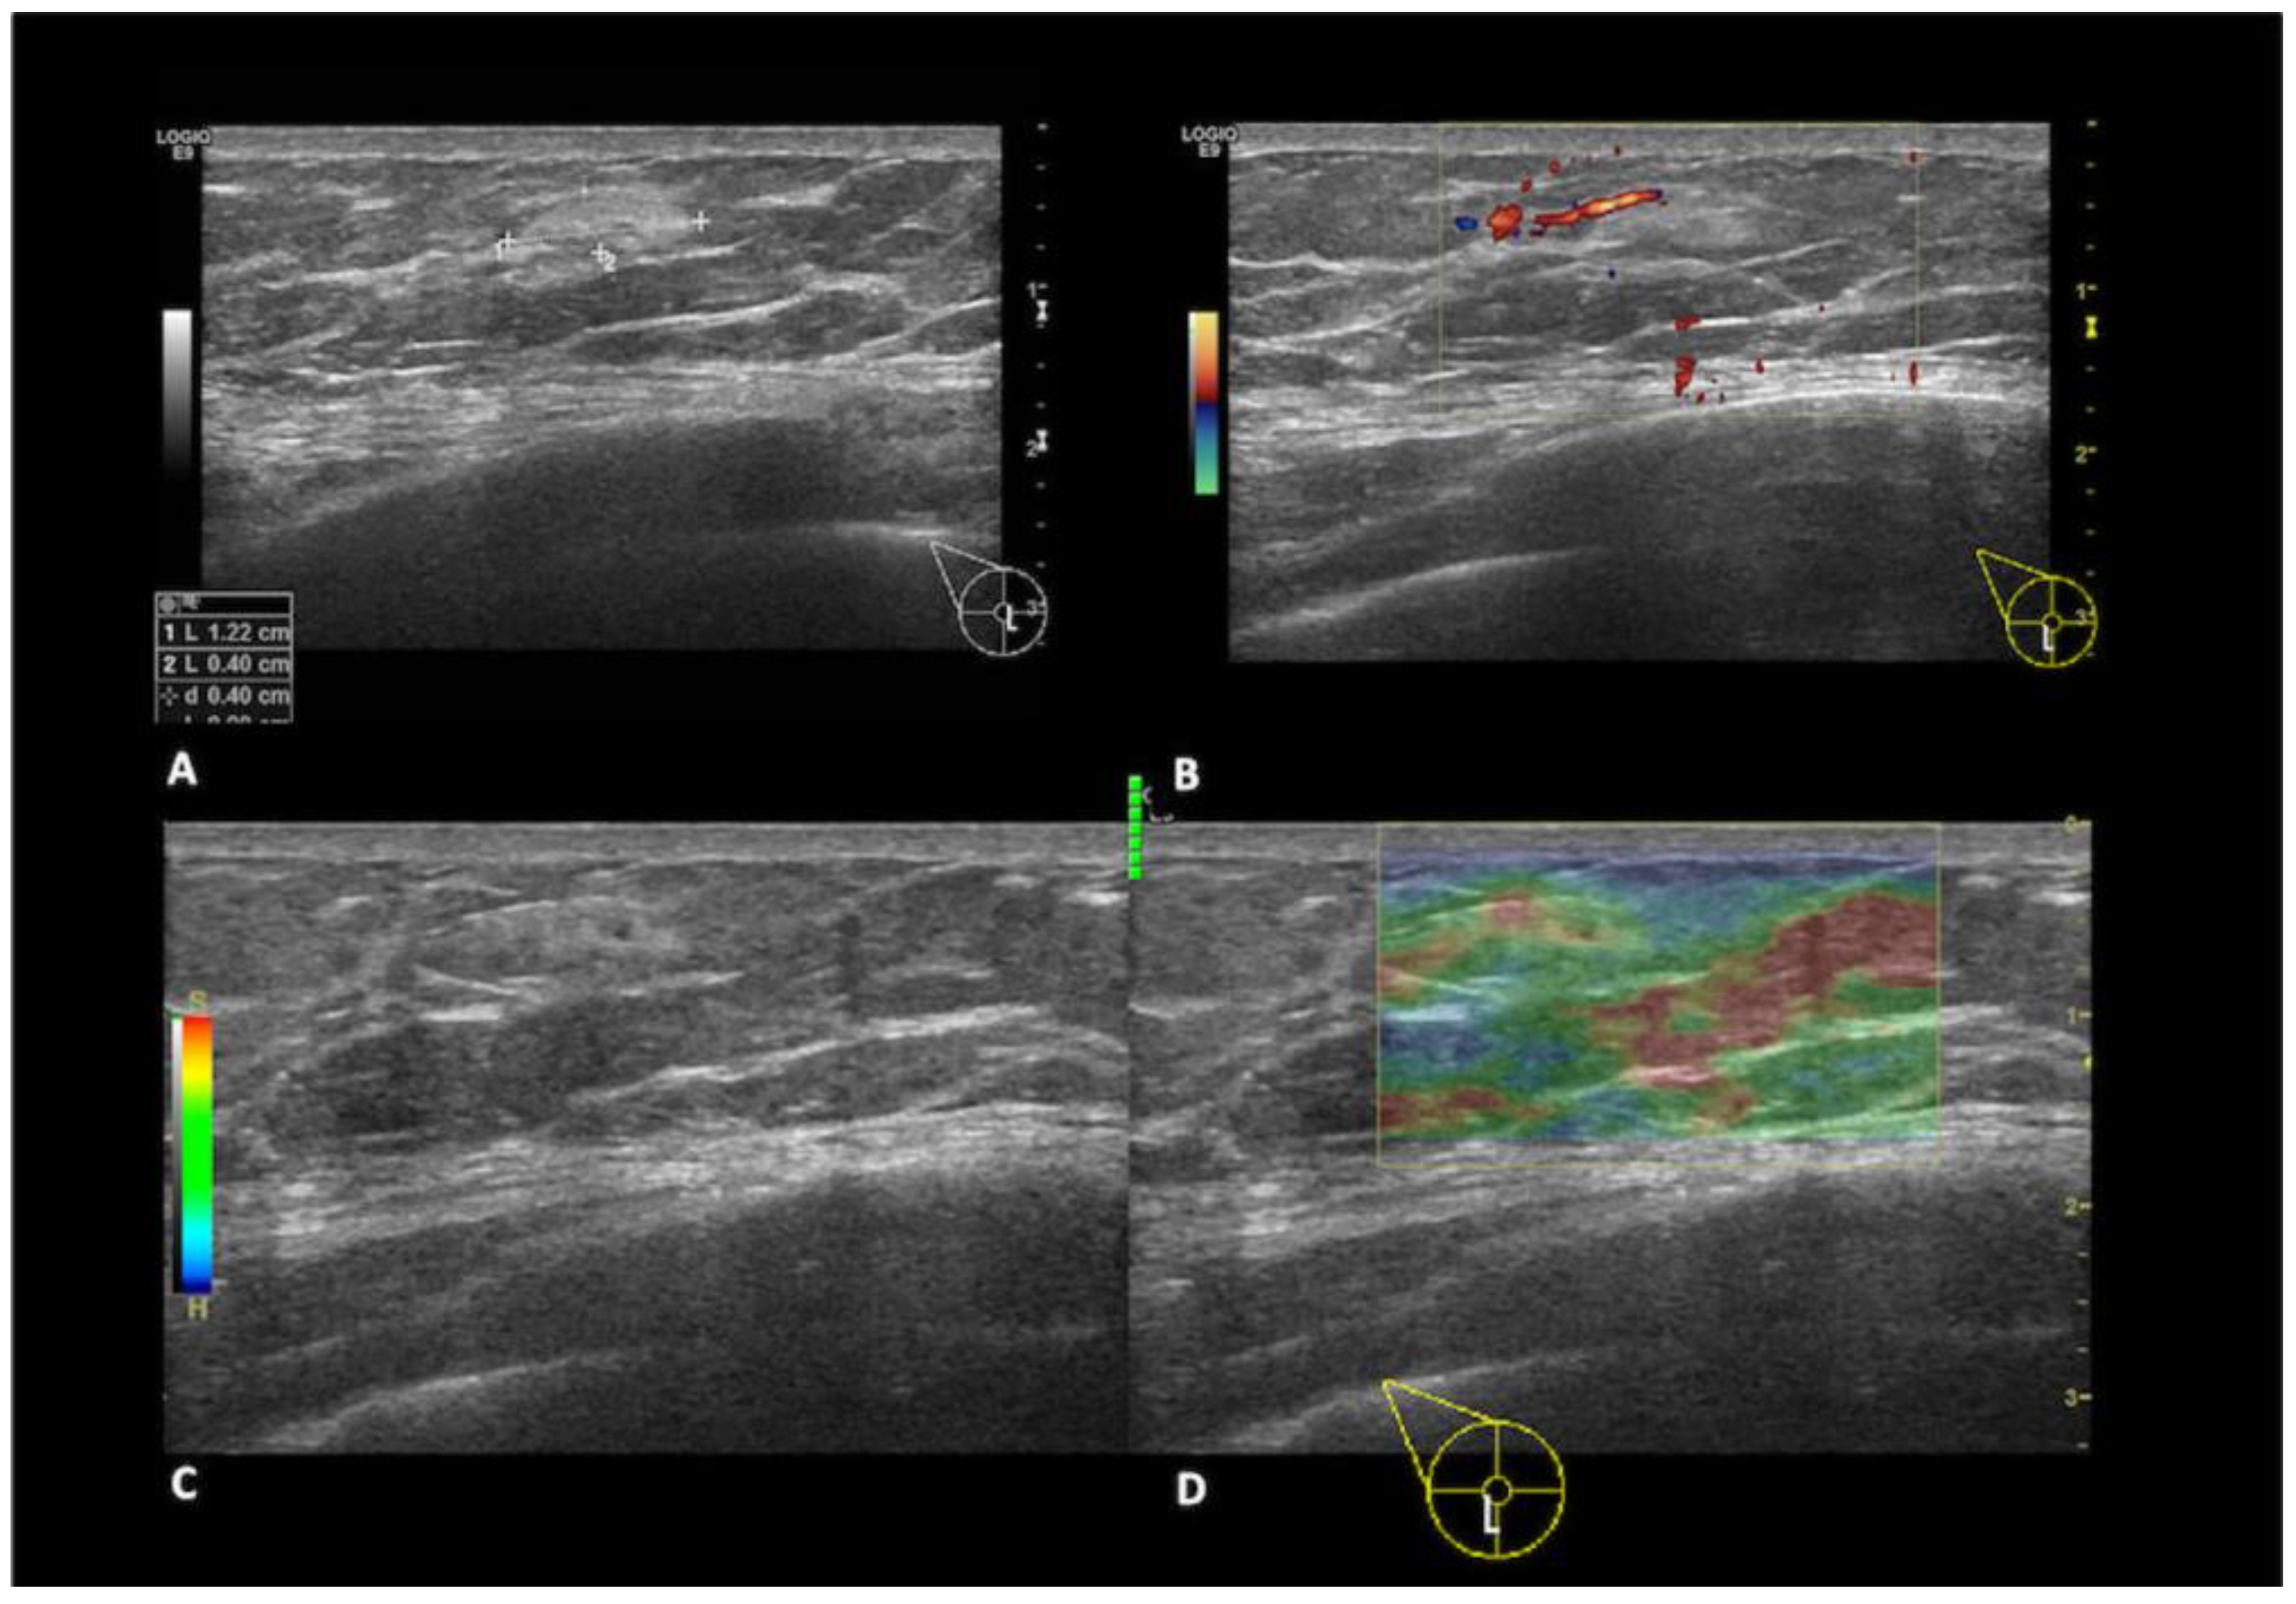

Epidermal cysts, also referred to as sebaceous cysts, represent the third most prevalent benign lesions in the MB. They arise from occluded hair follicles and appear as well-defined oval masses beneath the skin on mammography. Ultrasound examination reveals a homogeneous or heterogeneous hypoechoic oval lesion with no detectable vascular flow. The diagnosis is highly likely if the lesion exhibits a connecting part with the skin [17]. Fat necrosis is a benign condition often resulting from trauma, biopsy, or surgery (Figure 4). Various imaging findings can be attributed to fat necrosis depending on the stage of necrosis [5]. Mammographically, it can manifest as an oil cyst, presenting as a round, circumscribed mass with a thin calcified rim. In some cases, it may appear as an oval mass associated with microcalcifications or coarse calcifications, posing a challenge in ruling out a malignancy. Sonographic features of fat necrosis vary, ranging from echogenic mobile internal bands to solid masses or complex masses with nodules [18].

Figure 4.

A 49year-old patient with a history of a blunt trauma on the right breast. In the sub-areolar region (A) of the right breast, there is a hyperechoic mass with anechoic internal components and (B) no signs of vascularization at color-doppler. (C,D) Strain elastography evaluation shows that the mass has an intermediate elasticity. The findings are consistent with fat necrosis.